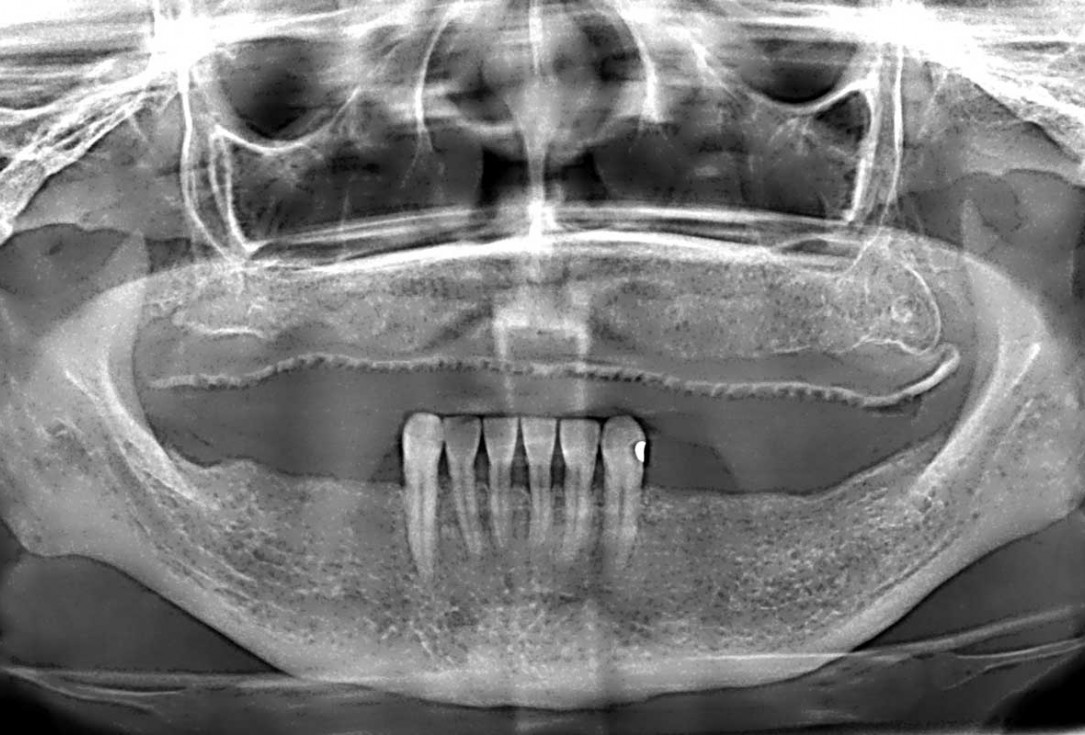

Initial x-ray showing bone loss around implants placed 5 years ago in another dental clinic